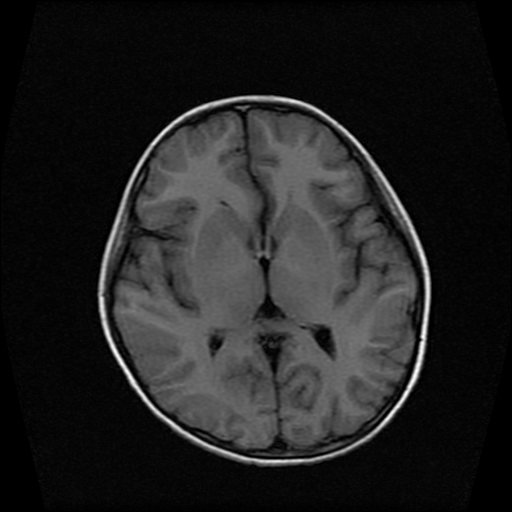

男性,12岁。反复头痛呕吐半月。脑积液无异常。病变部位ct值32hu,dwi无异常。

鞍内囊性占位性病变,t1wi、t2wi,均为高信号影。ct平扫为等密度。发病年龄较小。故首先考虑颅咽管瘤,可以做ct增强扫描

鞍内囊性占位性病变,t1wi、t2wi,均为高信号影。ct平扫为等密度。发病年龄较小。故首先考虑颅咽管瘤。